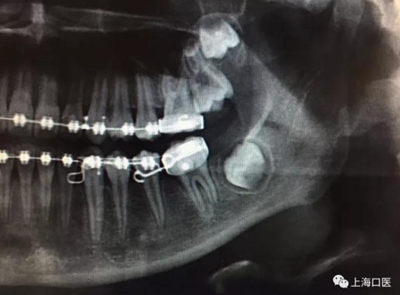

這是上海武廣增正畸工作室接診的一例非常規(guī)拔牙矯治病例,患者女性,初診年齡14歲。LL6殘冠拔除。LL7近中平移取代LL6,我們上傳了該患者一組下頜磨牙近中平移連續(xù)矯治過程的正畸X線片,與正畸界朋友分享。

來源:武廣增 上海口醫(yī)